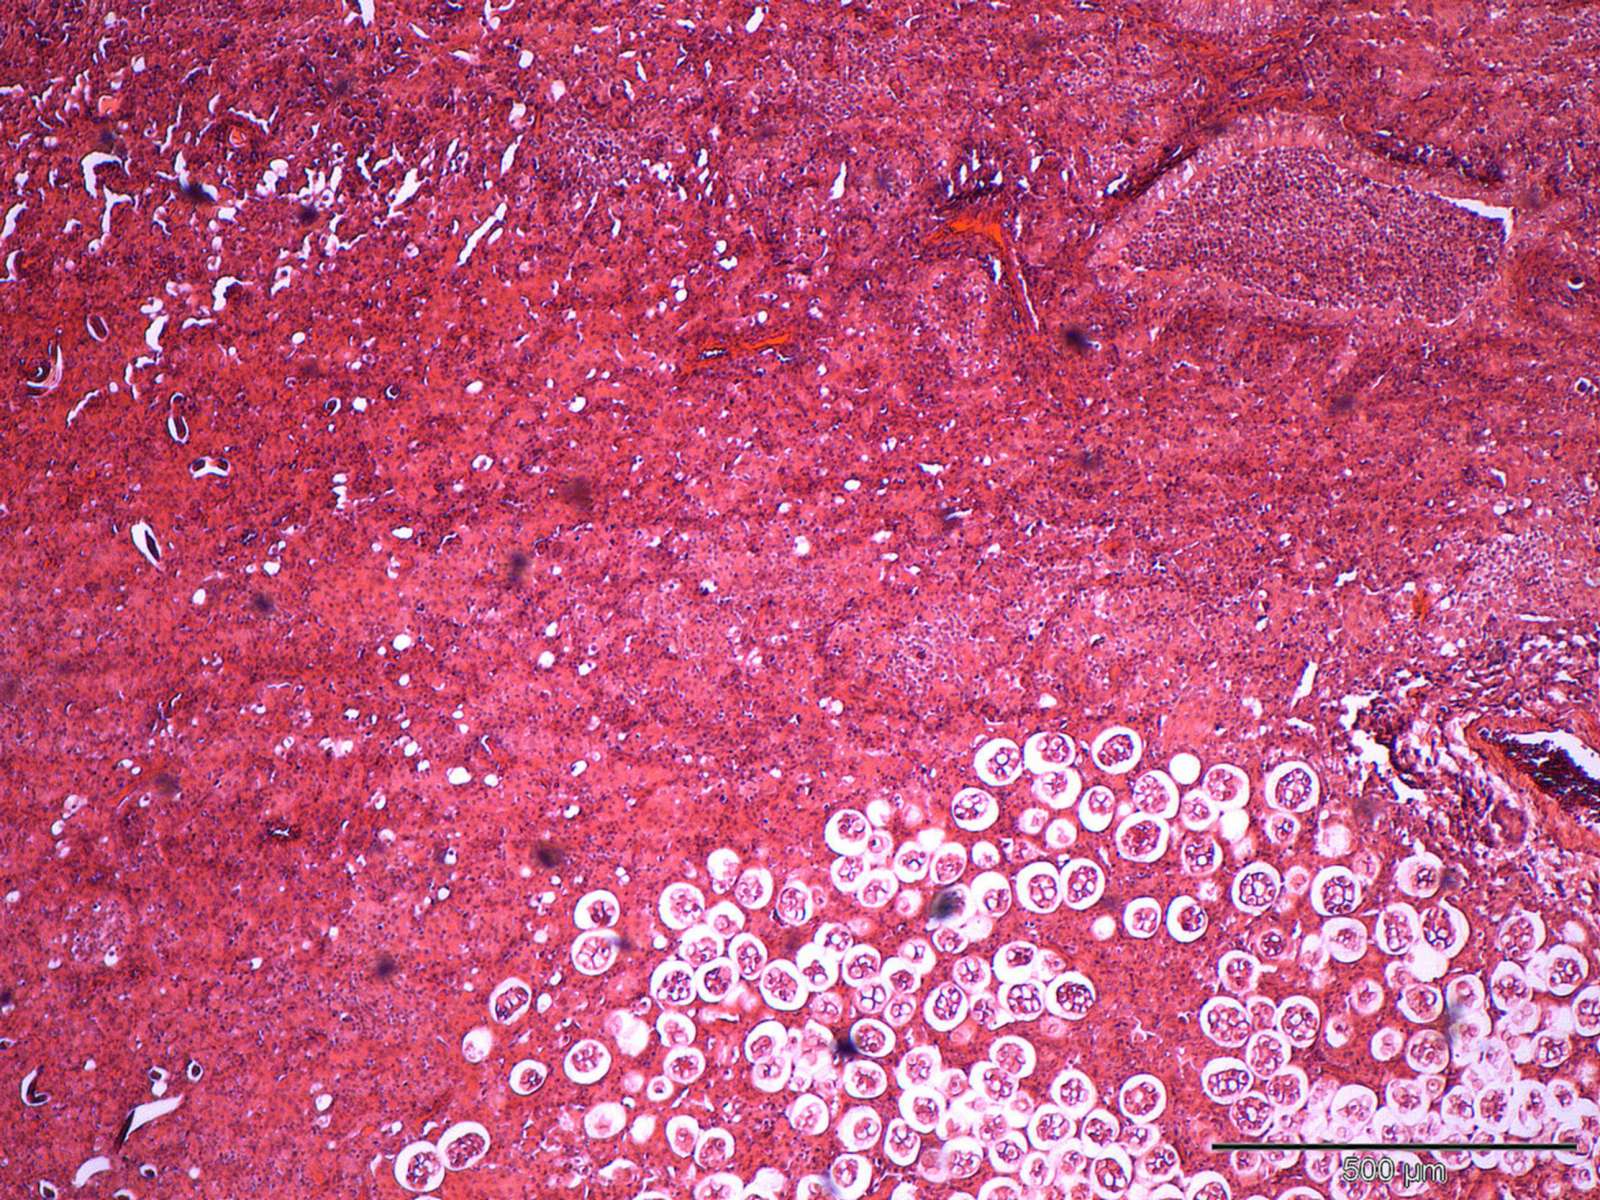

From stock.adobe.com

cat lung worm under the microscope Stock Photo Adobe Stock Cat Lung Worms Learn the signs and symptoms of lungworm in cats, like coughing and lethargy, and how to treat it. Lungworm infection of the lower respiratory tract, usually resulting in bronchitis or pneumonia, can be caused by any of several parasitic. Monthly treatment with nexgard spectra ® prevents lungworm infestations in cats, as well as providing. Lungworms in cats pose a serious. Cat Lung Worms.